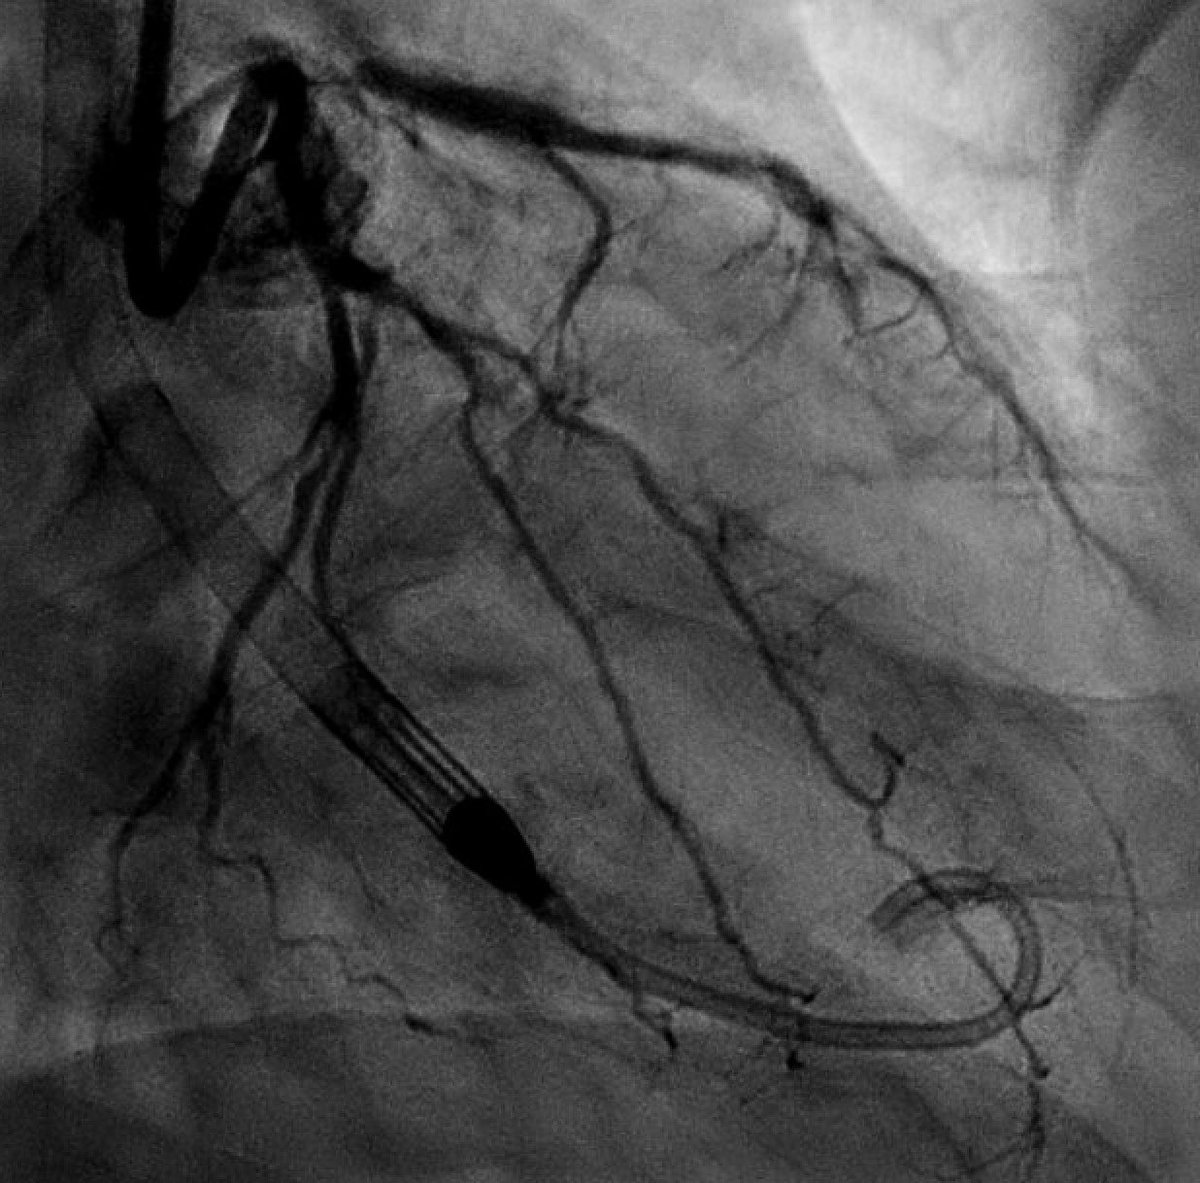

42 year old man, with a PMHx of HTN and HLD, who experienced chest pain but only came to the hospital at his wife’s behest. Time and again, we are reminded why married men have better cardiovascular outcomes: ahajournals.org/doi/full/10.11… #Cardiotwitter #InterventionalCardiology